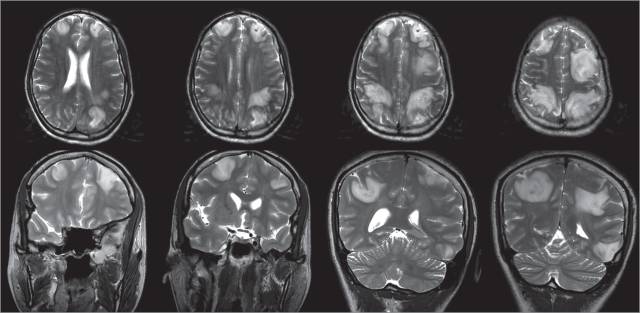

30余岁女性,因全面强直-阵挛发作持续3分钟被私家车送至急诊室。Glasgow昏迷量表评分9分。患者没有发热,生命体征平稳,搬动四肢时似有疼痛感。血糖133mg/dL(换算为mmol/L乘以0.0555)。患者朋友诉其在癫痫发作前使用过合成大麻。患者既往没有癫痫发作史,但4月前因为使用合成大麻出现过左侧大脑缺血性卒中和心肌梗死,症状和神经系统功能缺失已经缓解。患者入院后再次出现强直-阵挛发作,使用劳拉西泮和左乙拉西坦后好转。随后给予患者插管保护气道。以下实验室检查均正常:全血细胞计数,生化电解质,阿司匹林浓度,对乙酰氨基酚浓度,酒精浓度和肝功能检测。尿中药物筛查提示大麻阳性,脑脊液检查未做。头颅MRI提示双侧皮质和皮质下白质水肿。患者被转至重症监护室,神经系统检查结果逐步好转。24小时内脱离机械通气。7天后患者意识恢复正常,并无神经系统功能缺失,出院回家。因为没有医保,导致患者不能在神经科随访,也未复查头颅影像学。出于后90天电话随访,尽管在服用左乙拉西坦,患者诉仍然出现过2次自限性的发作。否认服用其他毒品。患者能独立正常生活,但因为乏力,无法持续站立超过20分钟。此外,患者因为持续存在的记忆问题和做事时难以集中注意力无法重返工作岗位。

(横断面及冠状位头颅MRI,T2WI,提示双侧弥漫的皮质及皮质下水肿)